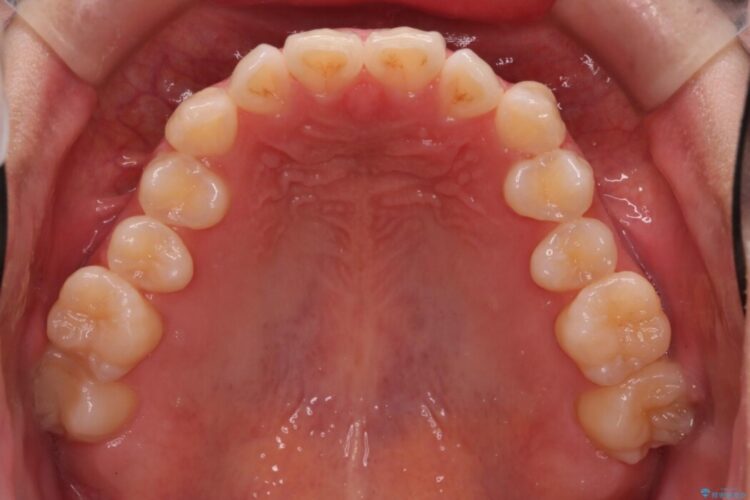

噛んだ時に上下の前歯の先端がちょうどぶつかってしまう切端咬合で、一番後ろの歯が辛うじて噛めている状態でした。

正常な噛み合わせだと上の前歯は下の歯に少しかぶさっています。

ですが切端咬合の場合は、上下の前歯がちょうどぶつかってしまっている状態を指します。